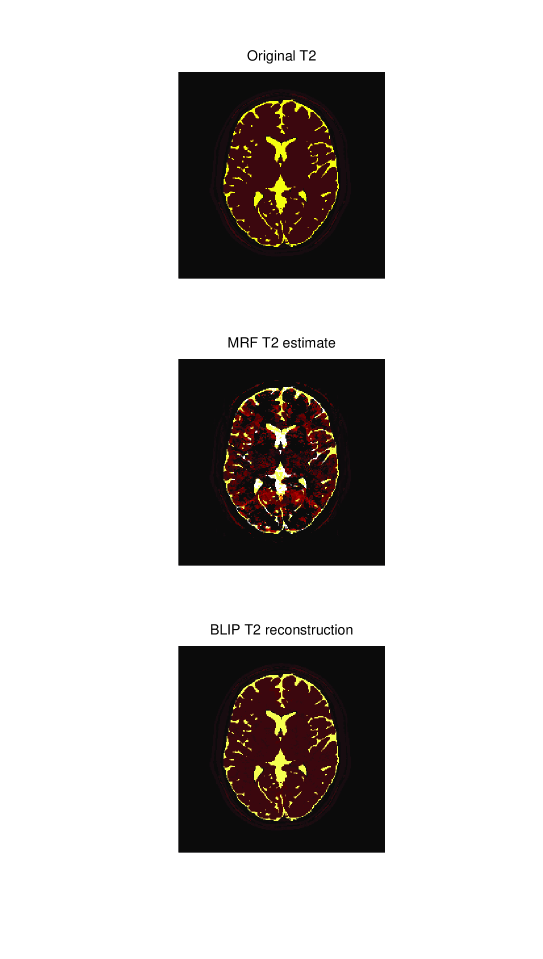

5.2.2 Visual Comparison

To get a visual indication of the performance of the BLIP approach over the MRF reconstruction at low sequence lengths, images of the 3 different parameter estimates for L=300𝐿300L=300 are given in figures 5, 6 and 7. The left hand column shows the ground truth parameter maps while the middle row shows the MRF reconstruction (scaled) and the right hand column shows the BLIP estimates (with spatial regularization). While the main aspects of the parameter maps are visible in the MRF reconstructions, there are still substantial aliasing artefacts. These are most prominent in the T1T1\operatorname*{T1} and T2T2\operatorname*{T2} estimates. In contrast, the BLIP estimates are virtually distortion-free, indicating that good spatial parameter estimates can be obtained with as little as 300 excitation pulses.

Refer to caption

Fig. 7: A visual comparison of the T2T2\operatorname*{T2} map estimates from a sequence of length L=300𝐿300L=300. The top plot shows the original T2T2\operatorname*{T2} map. The middle image is the MRF estimate and the bottom image is the BLIP estimate.